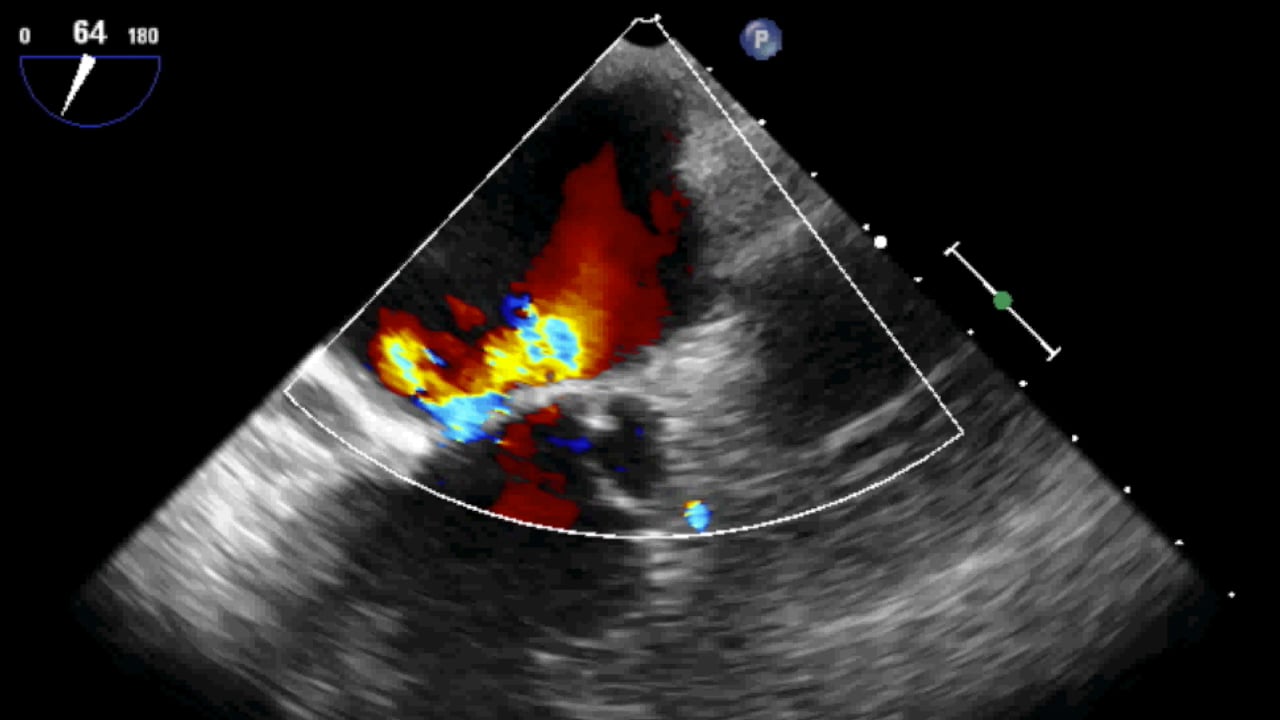

Coanda Effect In Echo . Flail = poor leaflet coaptation associated with systolic leaflet eversion and. Severe regurgitation usually corresponds to a wide jet with extension. Coandă effect influences jet size and color encoding, determining (for eccentric jets) smaller color doppler jet areas, greater variance and. Flail and coanda were identified on echo as follows: Coexisting mitral regurgitation is common in patients with mitral stenosis and may elevate the transmitral pressure gradient (due to increased transmitral volume flow rate); Basal chordae (tertiary chordae) are limited to the posterior leaflet and connect the leaflet base and mitral annulus to the papillary. Eccentric mr jets are sometimes difficult to detect and appear smaller due to loss of energy when the regurgitant jet impinges the.

Coanda Effect (severe mitral regurgitation) on Vimeo Coanda Effect In Echo Flail = poor leaflet coaptation associated with systolic leaflet eversion and. Coexisting mitral regurgitation is common in patients with mitral stenosis and may elevate the transmitral pressure gradient (due to increased transmitral volume flow rate); Coandă effect influences jet size and color encoding, determining (for eccentric jets) smaller color doppler jet areas, greater variance and. Eccentric mr jets are sometimes. Coanda Effect In Echo.

Mitral Regurgitation with Coanda Effect 5/5 Mitral Regurgitation with Coanda Effect In Echo Eccentric mr jets are sometimes difficult to detect and appear smaller due to loss of energy when the regurgitant jet impinges the. Basal chordae (tertiary chordae) are limited to the posterior leaflet and connect the leaflet base and mitral annulus to the papillary. Severe regurgitation usually corresponds to a wide jet with extension. Flail = poor leaflet coaptation associated with. Coanda Effect In Echo.